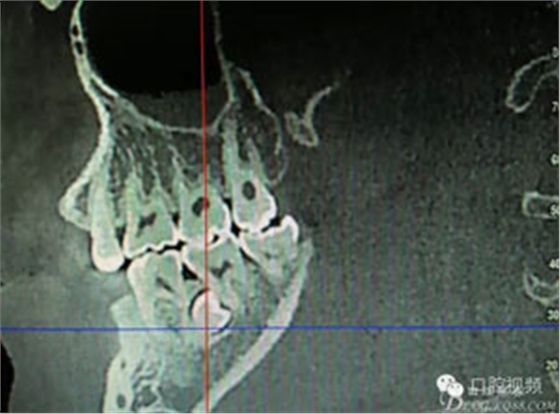

圖2.術(shù)前的CBCT,35移位至36、37之間的舌側(cè)。

患者、盧xx、男、19歲。主訴:左側(cè)下頜乳磨牙未脫落,要求檢查。??茩z查:左側(cè)下頜第二乳磨牙有充填物。無松動,全景片檢查。35移位至36、37之間。頰舌側(cè)均不能觸及隆起。CBCT檢查:35位于36、37的舌側(cè)。表面骨質(zhì)約2mm左右。35完全骨埋伏,36的遠中牙根疑是吸收。建議35暫觀察。置留不取。患者要求拔除擔(dān)心壓迫36牙根或者發(fā)生囊性變。術(shù)前簽手術(shù)同意書。